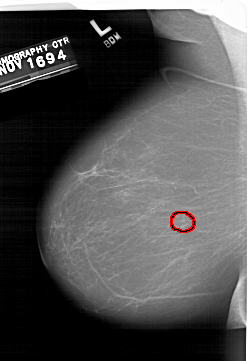

A_1406_1.LEFT_CC

LEFT_CC LINES 6856 PIXELS_PER_LINE 4381 BITS_PER_PIXEL 12 RESOLUTION 43.5 OVERLAY

FILE: A_1406_1.LEFT_CC.OVERLAY

TOTAL_ABNORMALITIES 1

ABNORMALITY 1

LESION_TYPE CALCIFICATION TYPE PUNCTATE DISTRIBUTION CLUSTERED

ASSESSMENT 4

SUBTLETY 4

PATHOLOGY BENIGN

TOTAL_OUTLINES 1

BOUNDARY